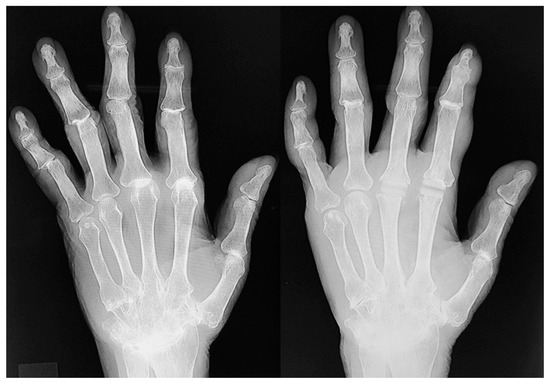

Trends in Rheumatoid Hand Surgery: Indications, Techniques, and Outcomes

by Masanori Nakayama, Yasuhiro Kiyota, Soichiro Nakamura and Mitsuru Yagi

J. Clin. Med. 2025, 14(2), 319; https://doi.org/10.3390/jcm14020319 - 7 Jan 2025

Rheumatoid arthritis (RA) causes persistent synovitis and arthritis, resulting in joint deformity and destruction throughout the body. As RA medications have evolved over the past 30 years, the surgical indications and techniques for RA joint deformities have changed. The aim of this review [...] Read more.

Rheumatoid arthritis (RA) causes persistent synovitis and arthritis, resulting in joint deformity and destruction throughout the body. As RA medications have evolved over the past 30 years, the surgical indications and techniques for RA joint deformities have changed. The aim of this review article is to summarize the recent trend of surgery for rheumatoid hand/finger deformities in previous reports and to present our recent surgical methods and outcomes for these deformities. A typical hand and finger deformity caused by RA is ulnar deviation, which is mainly caused by joint laxity and dislocation of the metacarpophalangeal joints, in addition to extensor tendon dislocation and/or wrist joint deformity. Although the incidence of hand/finger deformity and ulnar deviation caused by RA is decreasing due to advances in RA medications, patients with long-term RA or those with difficult-to-treat RA may still develop hand/finger deformity and ulnar deviation. If the hand/finger deformity is mild, it can be reduced manually, and conservative treatment with orthoses or splints may be required. If joint pain is severe despite good medical control of RA, or if the patient hopes to improve the appearance of the hand or fingers, surgical intervention is required. If there is only subluxation of the joints, which preserves their structure, reconstruction with only soft tissue surgery may be required. For example, for swan-neck deformity and boutonniére deformity, two of the most typical finger deformities due to RA, when the joint structures are almost intact and can be corrected manually, we opt for a surgical procedure that involves only soft tissue manipulation without the use of prosthetic implants. For ulnar deviation without joint destruction, we usually use a soft tissue-only surgical procedure. Our results have shown that the soft tissue-only surgery for ulnar deviation is as effective as joint replacement with implants. If the destruction of the joint has occurred and its dislocation/subluxation cannot be reduced manually, implant arthroplasty becomes necessary. If the joint destruction is severe, only intra-articular arthrodesis is required. In the era when RA can be controlled by medication, the hand surgeon should not overlook the change in the stage of the rheumatoid hand and should perform surgical intervention via the appropriate surgical method. Full article

Show Figures

Figure 1